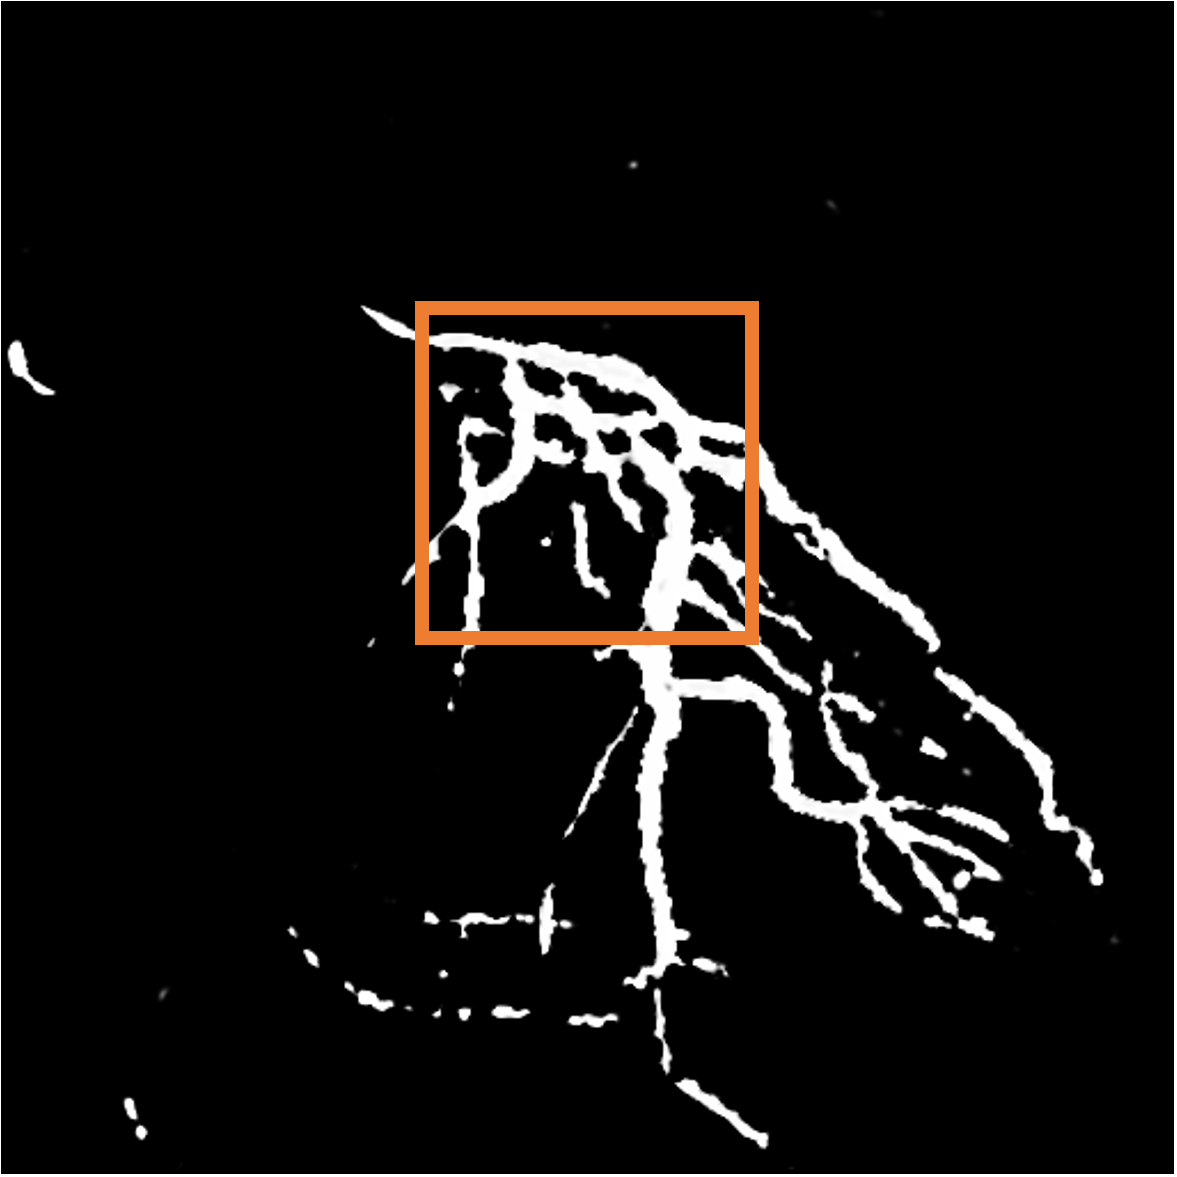

![]() |

| (a) Vessel mask | (b) Distance transform | (c) Vessel motion |

Parallel loss. Clearly, the direction of blood flow should align with the course of blood vessels (Fig. 4). Hence, we design the parallel loss to achieve a parallel alignment between them. Initially, we conduct skeletonization and distance transform on the masks obtained from Sec. 3.1, and calculate pixel-wise cosine similarity between these transformed masks and the predicted flow:

| (3) |

where represents the value obtained from the distance transform at pixel coordinate , and are the image gradients from the two spatial directions, and denotes the predicted flow value at position .